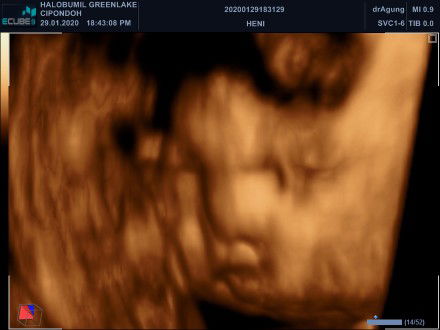

USG 33w4d

di Tap usia nya 31w6d di USG sudah 33w4d . Alhamdulillah si tembem sehat❣️?